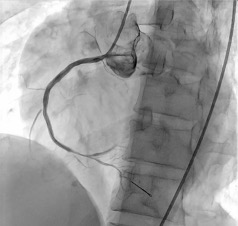

Procedural Step

Percutaneous coronary intervention was initiated. A Xience Alpine 3.0 x 38mm drug-eluting stent (DES) was positioned at the mid to distal RCA and deployed at 16 atm and post-dilated using the same stent balloon inflated at 18 atm. Another Evermine 3.5 x 48mm drug-eluting stent (DES) was positioned at the proximal RCA and deployed at 18 atm and post-dilated using the same stent balloon inflated at 18 atm. Further dilation of the distal RCA was done using a Mini Trek 2.0 x 15mm balloon and inflated at 12 atm. However, j ust a few minutes after placing the stent. There was noted recurrence of the ST elevation on the cardiac monitor. A second look angiogram was immediately performed to check the patency of the stents. Immediately, manual distal displacement using the same stent balloon was done to displace the thrombus. Repeat angiogram showed TIMI II flow on the right coronary artery and resolution of the ST segment elevation.